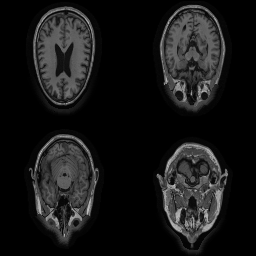

| Original | Renderings after de-identification | Original | MRI slices after de-identification | ||||||

| CP-GAN | FACE MASK | DEFACE | QUICKSHEAR | CP-GAN | FACE MASK | DEFACE | QUICKSHEAR | ||

Benchmark De-Identification Methods. We compare our result with three publicly available and widely-established methods for de-identification of MRI head scans, depicted in Figure 3. All methods have in common that they (1) are not deep-learning-driven, (2) require no additional training and (3), are used on a day-to-day basis in neuroscience and clinical research. All procedures were applied with default settings on images of resolution . The methods include QUICKSHEAR [Schimke et al.(2011)Schimke, Kuehler, and Hale], FACE MASK [Milchenko and Marcus(2013)], and DEFACE [Bischoff-Grethe et al.(2007)Bischoff-Grethe, Ozyurt, Busa, Quinn, Fennema-Notestine, Clark, Morris, Bondi, Jernigan, Dale, Brown, and Fischl]. Descriptions of the methods are provided in the Appendix. We also include MRI WATERSHED [Ségonne et al.(2004)Ségonne, Dale, Busa, Glessner, Salat, Hahn, and Fischl], a skull-stripping method that removes everything except the brain.